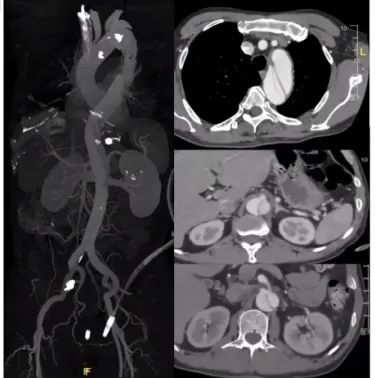

患者男性,63岁,急性胸痛5小时入院。该患者从主动脉弓部直到髂动脉撕裂的 B型夹层,为全程三阶段管理的病例。第一阶段进行降主动脉几乎全程覆盖。在第二阶段真腔狭小,下肢有缺血的表现,行3D打印模型下的F/B EVAR手术。第三阶段在做完主髂段后再做主髂,尽量保髂内动脉重建。采用激光原位技术将双侧髂内动脉全部保留,减少髂内动脉对脊髓缺血的影响。手术中发现出现假腔II型内漏,内漏相对较小可以随访观察。最近随访观察肠系膜下动脉内漏完全消失。

第一次治疗(2021.02.01)

第二次治疗(2021.09.02)

第三次治疗(2021.10.28)

术后复查(20220702)

II型内漏大部分消失